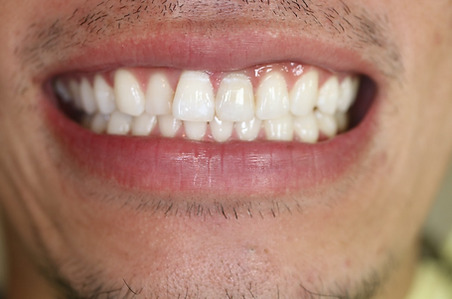

1矯正・マウスピース【治療例1】

治療前

治療後